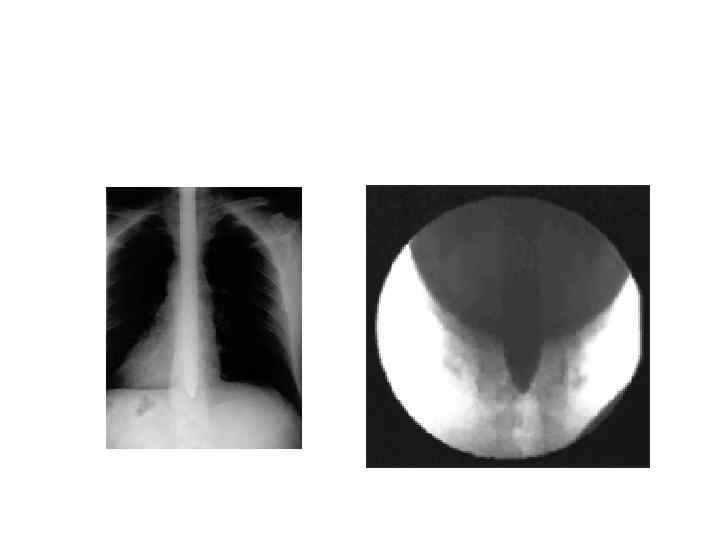

Рентгенограмма пищевода при ахалазии кардии: • видны резко суженный терминальный отдел пищевода, супрастенотическое расширение пищевода; газовый пузырь желудка не определяется.

Рентгенограмма пищевода • а — при тугом наполнении контрастной массой; • б — при малом наполнении (видны складки слизистой оболочки